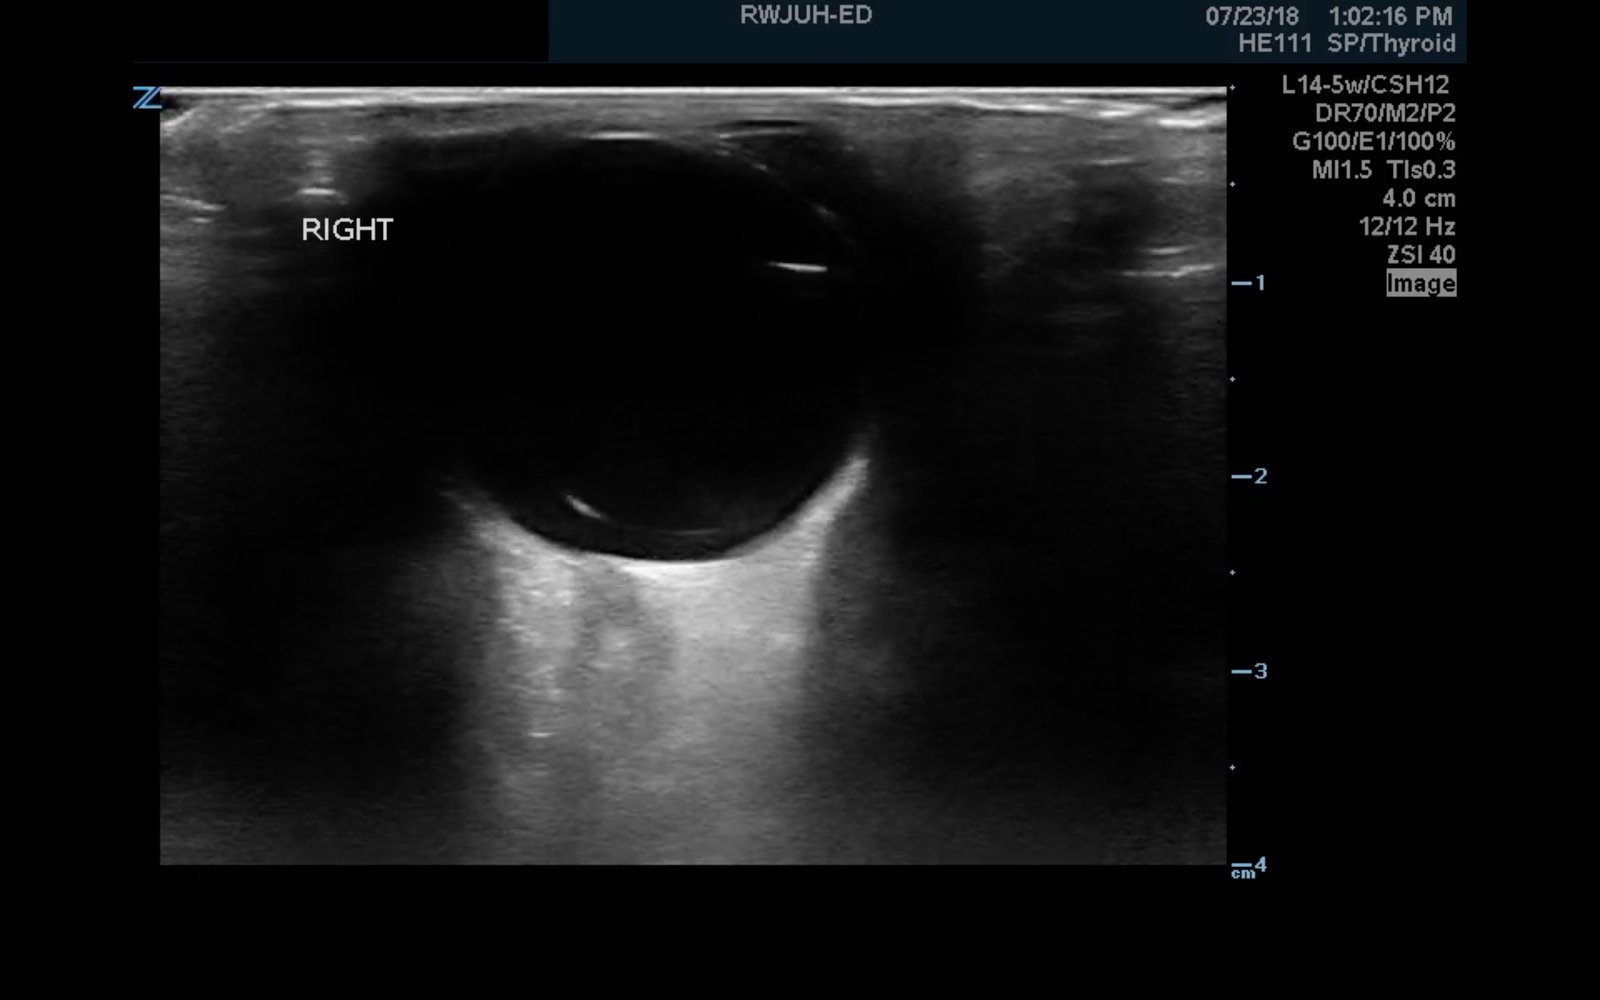

Ocular ultrasound was performed and demonstrated a thin, slightly echogenic strand (blue arrow) extending from the posterior eye into the vitreous humor (yellow arrow) which was hyperkinetic with extraocular motion. These findings are consistent with a posterior vitreous detachment (PVD).

Retinal detachment presents in ocular ultrasound as a taut, hyperechoic strand that moves in conjunction with extraocular movement. Posterior vitreous detachment presents as a much thinner and less echogenic strand that is hyperkinetic and wave-like with extraocular movement, described as swaying seaweed in appearance.6,7,8,9